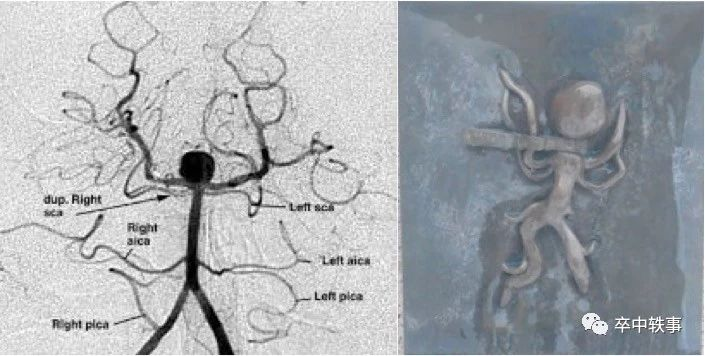

另外,Drake 发明了以他命名的 “动脉瘤夹 - Drake-Clip”(下图右)。

后循环(上图左)动脉瘤手术难做,一是位置深,入路难;二是紧贴脑干和小脑,风险大;三是病人少,多数神外医生没有后循环动脉瘤手术的经验。

为了做复杂的基底动脉瘤手术,Drake 使用人工低温和短时停止心脏循环,需要強大的麻醉团队。Drake 报道了他的经验:“治疗后循环动脉瘤 - Drake CG. The Treatment of Aneurysms of the Posterior Circulation. Clin Neurosurg 26: 96-144, 1979(上图)”。